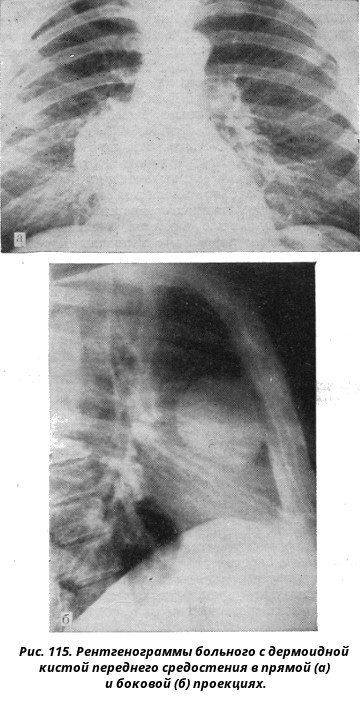

Рентгеновские снимки тератомы средостения: Диагностика и лечение

Раздел: Фотоэссе